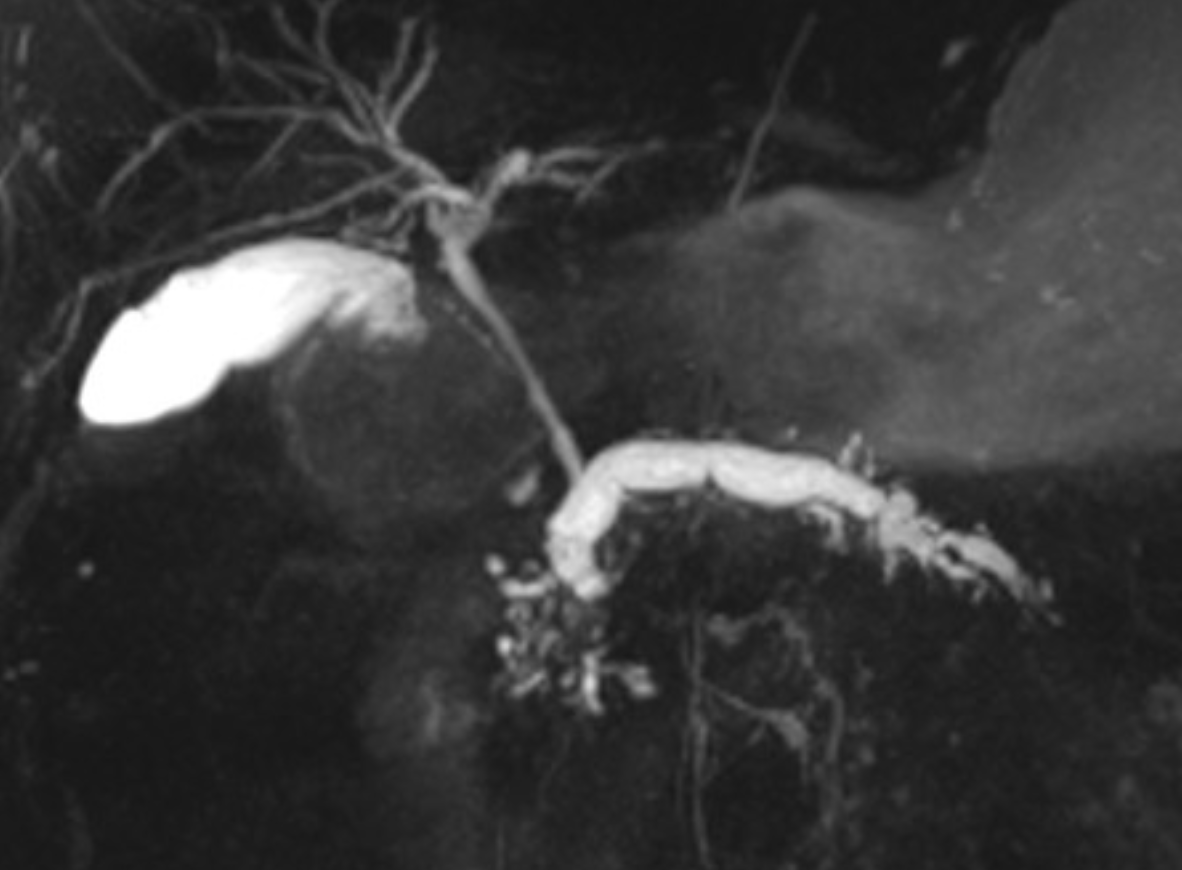

Replaced right hepatic artery (RHA) arising from the superior mesenteric artery (SMA).

Case Discussion

The right hepatic artery arises from the superior mesenteric artery (SMA), also referred to as “replaced to the SMA”, in 9 to 15% of the population. It is the most common variant in hepatic arterial anatomy.